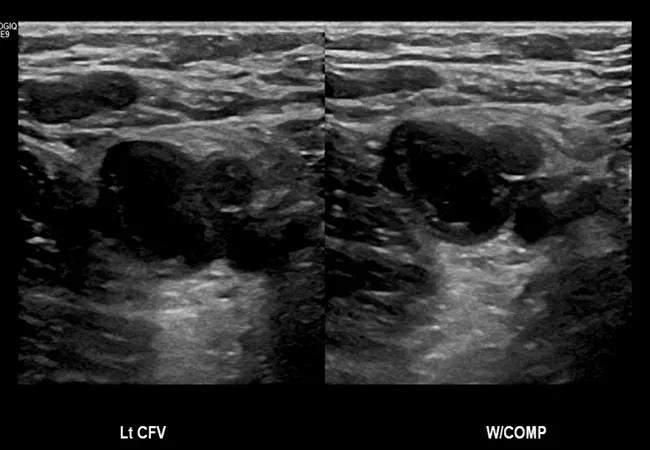

Figure. Ultrasound showing a thrombus in the left common femoral vein that is inhibiting compression of the vein.